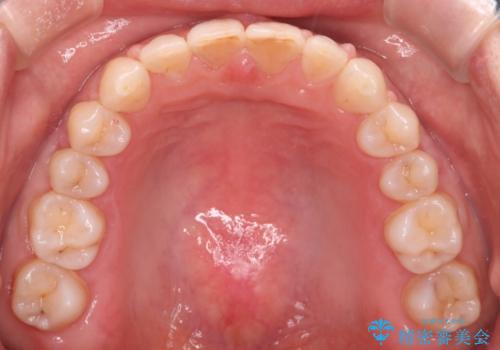

- 前歯のすきっ歯が気になるということで来院されました。今回は抜歯はしないためワイヤー矯正かインビザライン矯正のどちらでも治療可能でしたが、患者さまのご希望により表のワイヤー装置にて治療をおこないました。

前歯に隙間がいくつかあったため、今回は上下でゴムかけを行いスペースを埋めるための力をかけて閉じました。もう少し早く終了する予定でしたが、ブラッシング不良による歯肉腫脹があり、一部スペースクローズに時間がかかりました。